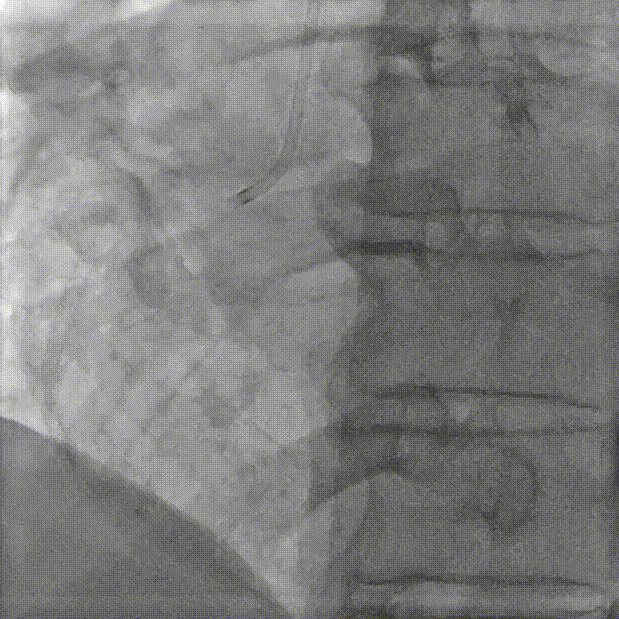

3.超声MPR模式下攻入锚定部件。

MPR下攻入锚定部件